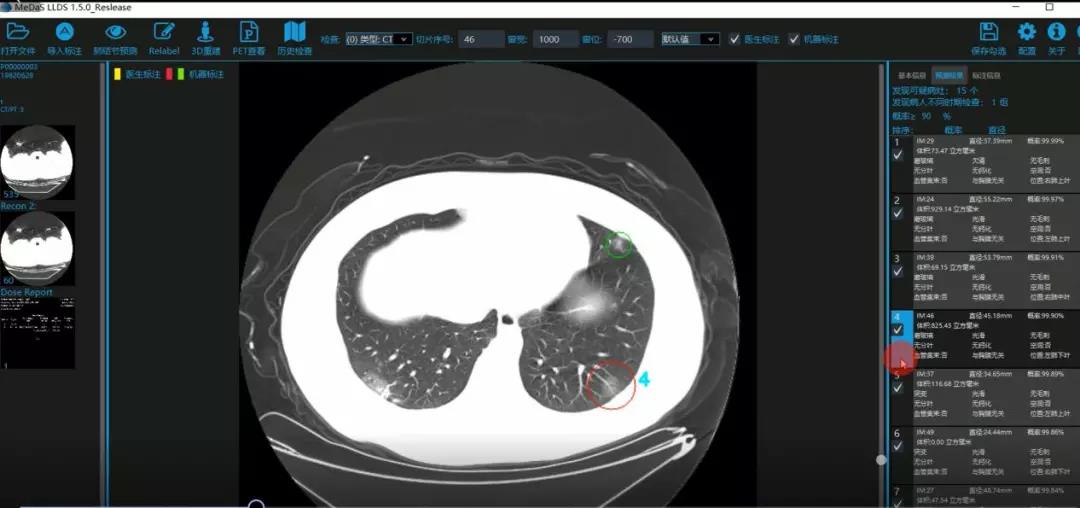

西电sunbet智能软件与系统新技术研究所副教授张亮的爱人是西安交通大学第二附属医院抗疫一线的影像科医生,疫情发生以来,他们讨论最多的就是新型冠状病毒感染者的早期诊断问题。作为一名医护家属,身为高校科研工作者,张亮深知快速准确地诊断新冠肺炎早期患者对控制和防治疫情的重要性和挑战性。他与团队成员主动出击,通过远程网络会议,在前期医学影像处理的研究基础上加速科研攻关,反复讨论方案,屡次设计模型,与上海宽带技术及应用工程研究中心、上海交通大学医公司附属瑞金医院等合作单位的人员多次标注整理患者肺部CT影像数据到深夜。与此同时,他们依托上海瑞金医院、西安交通大学第二附属医院等的新冠肺炎疑似、确诊患者肺部CT影像,通过综合分析新冠肺炎患者的肺部CT影像特点(磨玻璃、体积大小、位置等特征),张亮团队加快技术攻关,设计开发了基于深度学习的新型冠状病毒的早期检测筛查模型系统。

对应新冠肺炎CT病灶检测效果

令人欣喜的是,通过对实际门诊数据排查测试,该模型可以减轻医护人员近80%的工作量,新冠肺炎患者的检测召回率超过95%。目前,模型系统正在进行最后的调试工作,很快投入到“战疫”一线,缓解医护人员紧缺、确诊检测工作耗时较长等问题,减少医护人员的工作时间和劳动强度,提高工作效率。